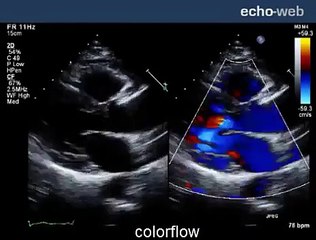

Aortic Valve Replacement

aortic heart surgery